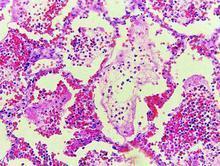

豬巴氏桿菌病2.急性型急性型病例主要表現為肺部炎症。肺小葉間質水腫、增寬,有不同發展時期的肝變區,病變部質度堅實如肝,切面有暗紅、灰紅、灰白或灰黃等不同色彩,呈大理石樣外觀。支氣管內充滿分泌物。胸腔和心包內積有多量淡紅色混濁液體,內混有纖維素。胸膜和心包膜粗糙無光澤,上附纖維素,甚至心包和胸膜或者肺與胸膜發生粘連。胸部淋巴結腫大或出血。

3.病理變化最急性病例,表現為敗血症的變化,咽喉部急性炎症變化,出血、水腫及膠凍樣浸潤。急性病例,主要為肺的纖維素性肺炎呈現的大理石樣病變,以及胸部淋巴結的炎症。慢性病例為肺部較陳舊的肺炎灶及胸膜肺炎。